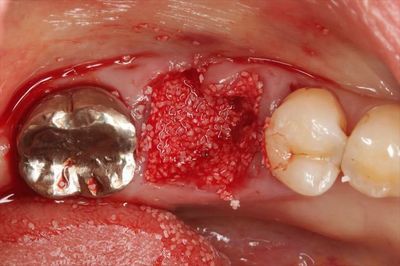

今後のインプラント治療に備えて骨補填材とサイトプラストを用いてソケットプリザーベーションを行います。

まずは骨補填材を抜歯窩に填入しました。

填入前に周囲の歯肉をエンベロープ状にわずかに剥離して準備しています。